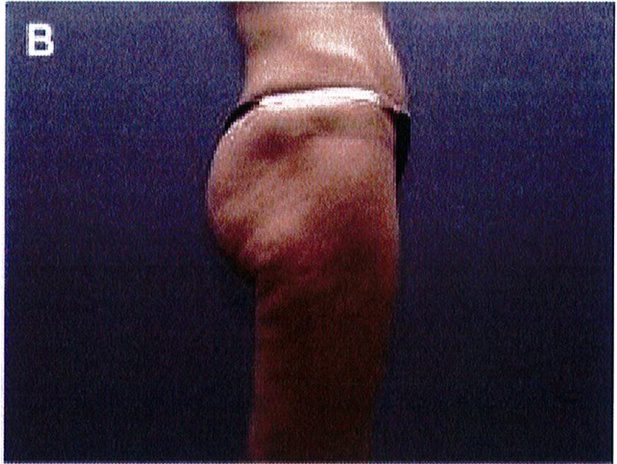

Hình. 11. (A, B) Bệnh nhân nữ 59 tuổi với vùng da mông chùng và xệ. (C,D) Hai năm sau phẫu thuật tạo hình thành bụng và tạo hình mông bằng phương pháp purse-string.Bênh nhân này bị tách vết mổ, sau đó đã đươc điều tri liền seo